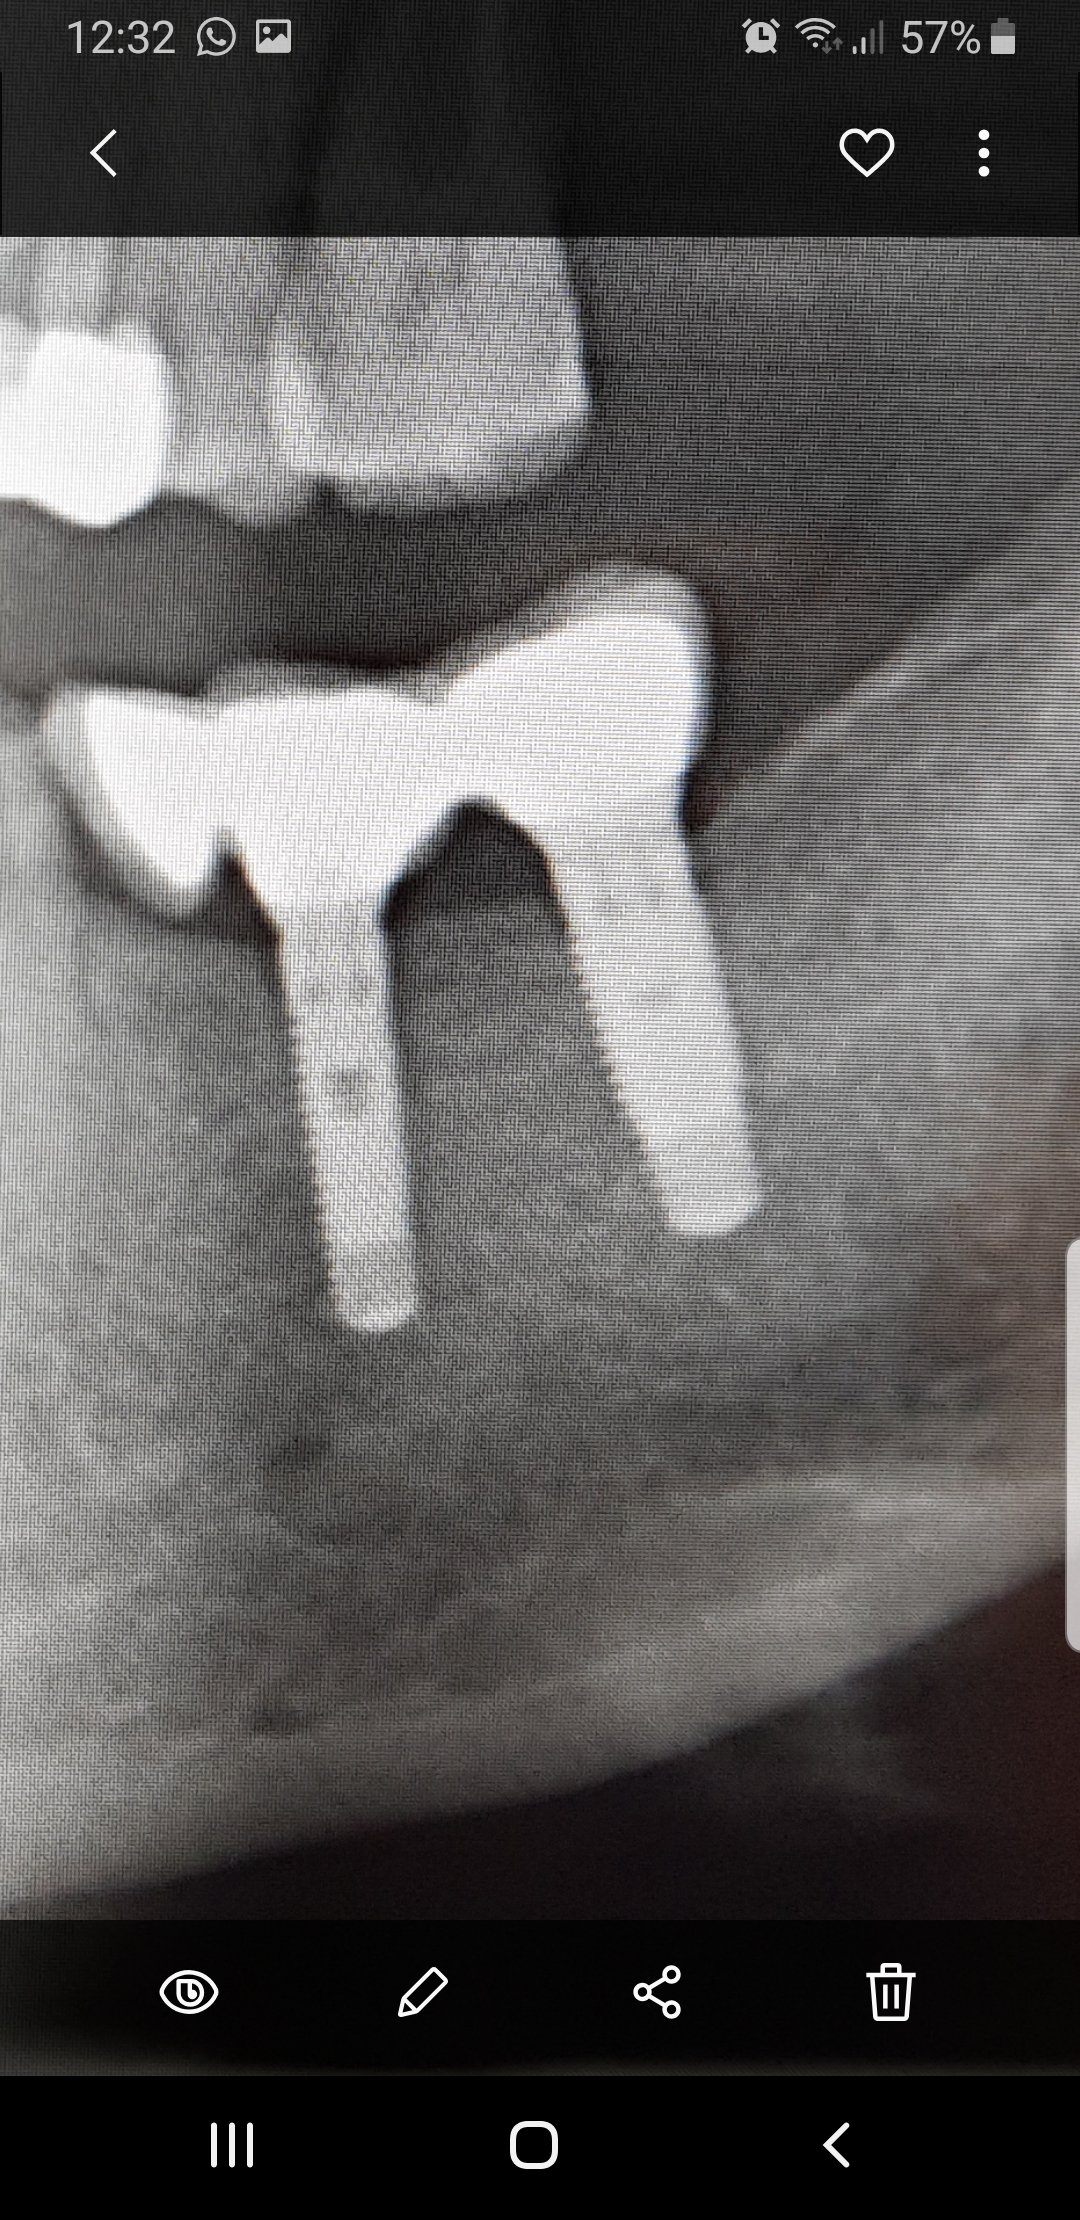

Implante colocado hace 8-11 años en Barcelona. se le cayó la corona cementada al poco de colocársela y se la cementaron de manera que no volvió a caerse hasta hace [...]